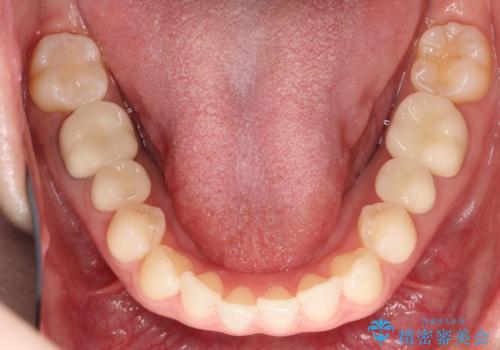

【メタルフリー】銀歯を白くしたい。オールセラミッククラウン。

- 銀歯を白くしたいと希望され来院されました。

すぐにでも白くしたいとのことで、2回目の来院で銀歯を白い仮歯に変更し喜んでいただきました。

ただ単純に白くするでけではなく拡大鏡を使用し、丁寧な処置を行なっております。